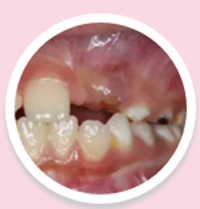

8歲的女孩欣欣

可愛的女孩欣欣同樣是曾經(jīng)有過乳牙外傷,現(xiàn)在發(fā)現(xiàn)左上門牙未萌出前來咨詢。

CBDT顯示:恒牙牙胚旋轉(zhuǎn)90度,牙根開始彎曲發(fā)育: